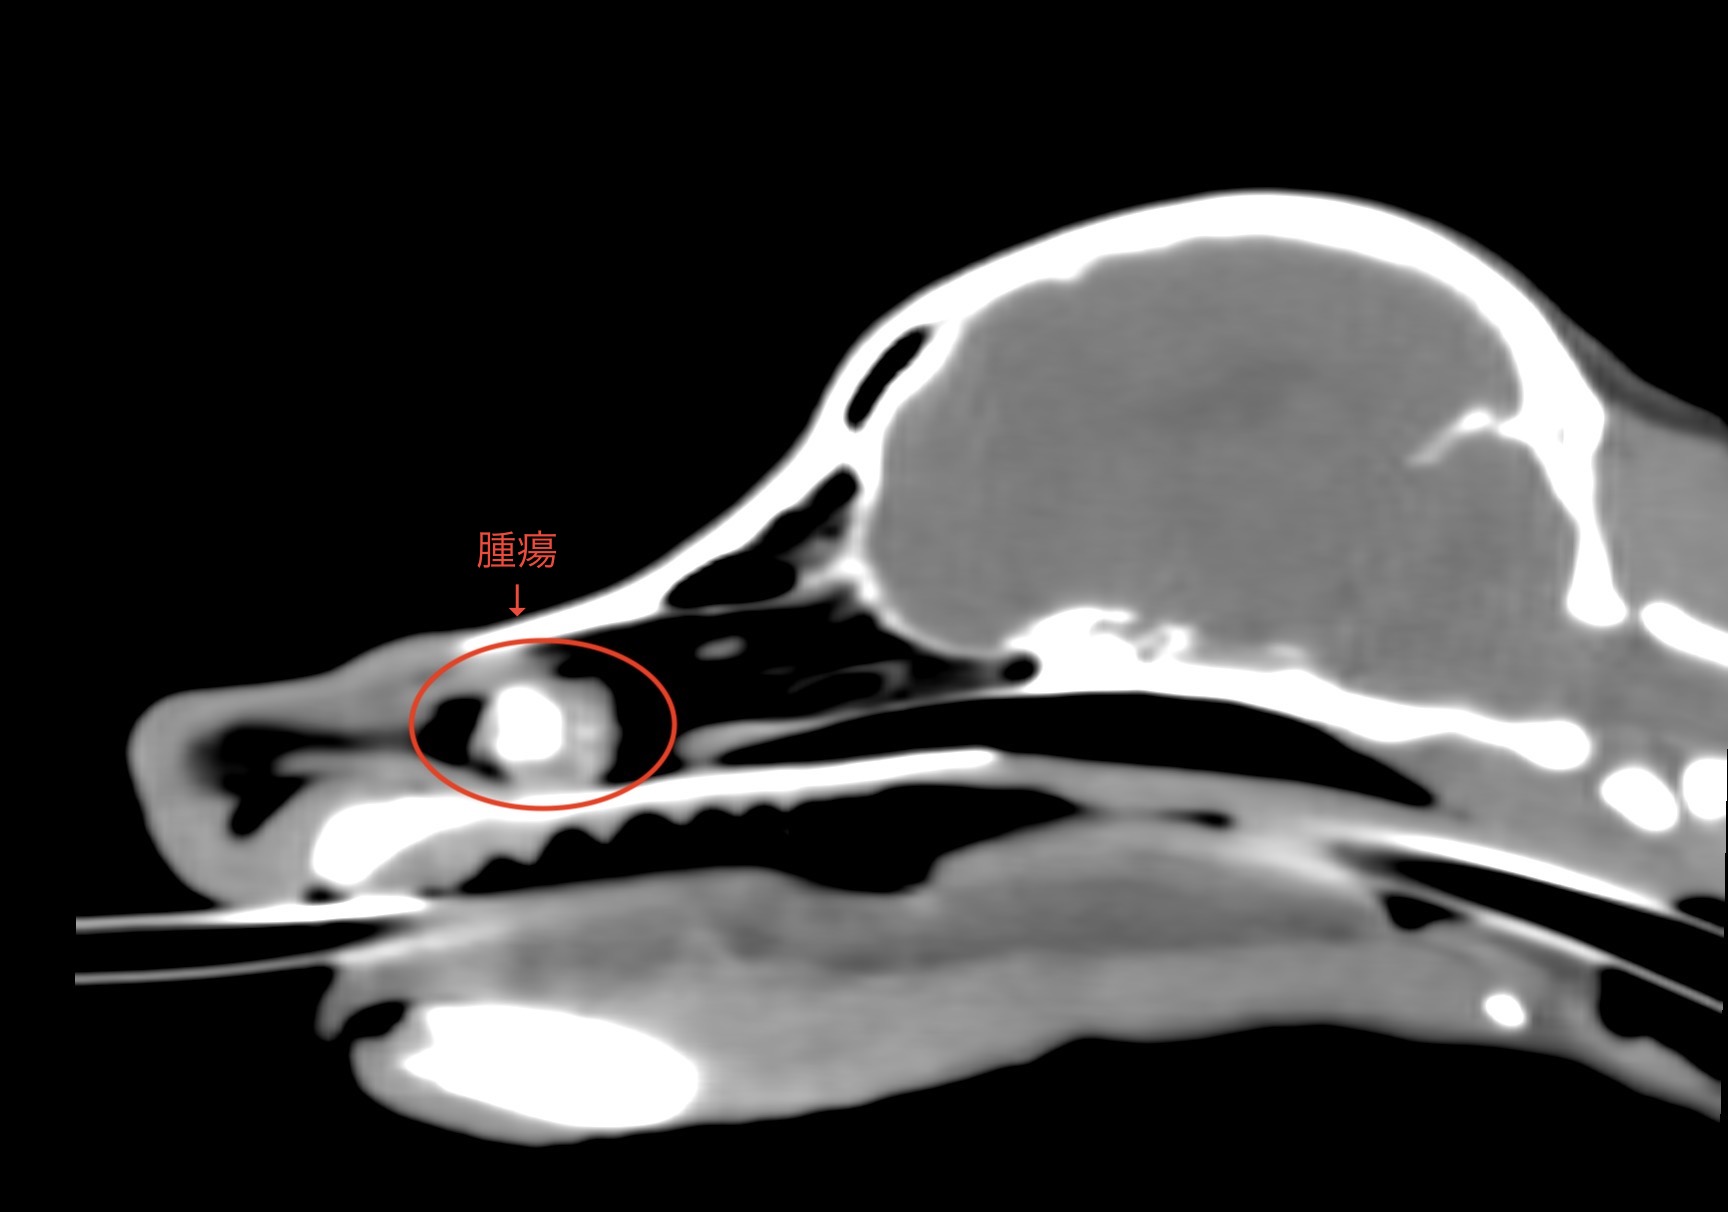

くしゃみの症状で来院された犬が、CT検査において腫瘍を発見した子を紹介します。

12歳のトイプードルで、2ヶ月前よりくしゃみに鮮血が混じるようになったとのことで来院されました。

下の画像がCT画像です。

レントゲン検査とは異なり明らかに左の鼻腔内に腫瘤が認められ、中隔を右側に圧迫しています。

鼻の出口から腫瘤を採取し、病理検査を実施したところ『軟骨肉腫』と診断されました。

本症例では放射線治療が適応と判断し、大学病院に紹介しております。